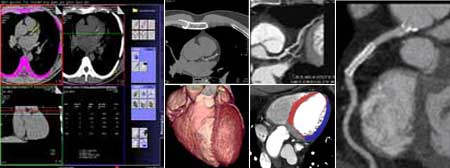

Koronarna CT angiografija

Kardiovaskularne bolesti su ubica broj jedan u današnjem svijetu i odnose svake godine više života nego sve maligne bolesti zajedno. Koronarna bolest je najčešće uzrokovana aterosklerozom (stvaranjem plakova u zidu krvnih žila uzrokojući njihvo suženje). Donedavno, nije postojao neinvazivni način da se direktno analiziraju koronarne arterije na prisustvo aterosklerotskih promjena. Razvoj tehnologije višeslojnog CT-a (MSCT/MDCT) omogućio je detaljno trodimenzionalno prikazivanje kucajućeg srca u toku jednog zadržavanja daha. U našem dijagnostičkom centru nudimo ovu tehniku pregleda koronarnih arterija, na multi-slice aparatu, s najmodernijim softverom i minimalnom dozom zračenja.

Šta je CT koronarografija?

To je metoda prikaza malih arterija koje hrane srčani mišić, upotrebom CT skenera, koji prikazuje protok krvi u koronarnim arterijama i kompjuterskog softvera da bi se dobio odgovarajući trodimenzionalni prikaz. CT angiografija je neinvazivni način da se prikažu zidovi koronarnih arterija I nadju eventualni aterosklerotski plakovi, što pomaže liječniku u odredjivanju rizika srčanog udara.